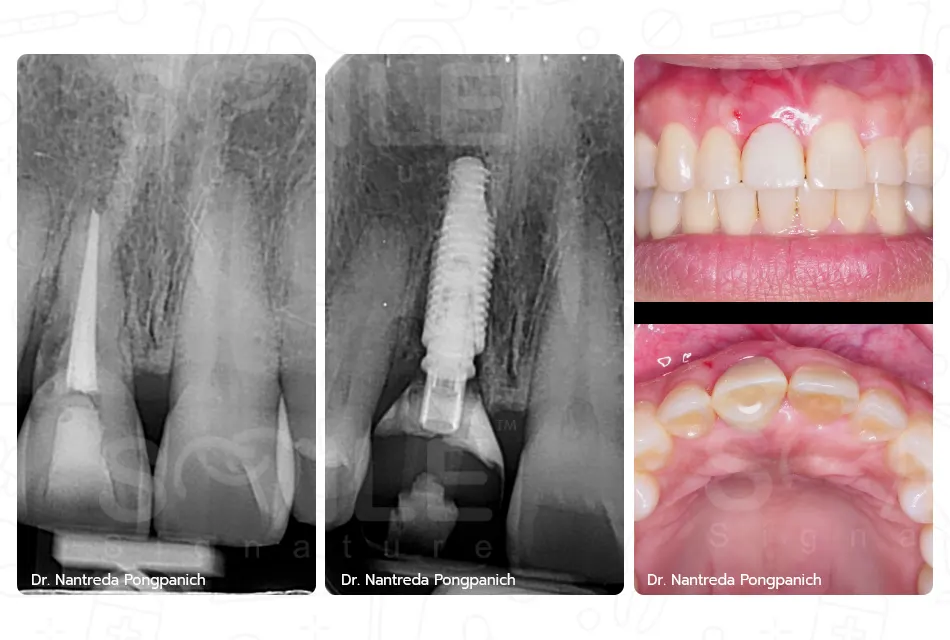

Image Box text